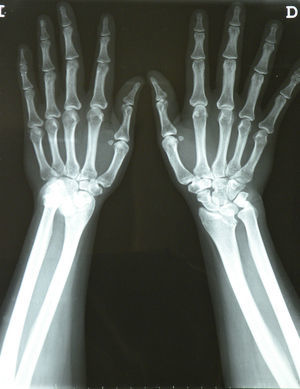

The posteroanterior wrist X-rays (Fig. 2) showed typical Madelung deformity changes on the right wrist1: shortening of the radius compared to the ulna, dorsally and radially curved radius, dorsal and radial convexity, an angle similar to the distal radial joint surface, a mismatch of the distal radioulnar joint and carpal dislocation. The lateral projection (Fig. 3) demonstrated anterior arching of the radius and dorsal dislocation on the ulnar head; the carpus was also dislocated on the ulnar side and anteriorly in the distal radioulnar joint, in a way that made the wrist bones appear to follow the arch of the radius.2 The patient was diagnosed with a carpal tunnel syndrome due to Madelung's deformity and was programmed for an evaluation by the orthopedics department but, due to a delay, medical treatment with local steroid infiltrations was carried out. 1ml of triamcinolone was injected into the right wrist using a standard technique.3 The pain improved in the next 2 days (VAS: 50/100), disappearing completely after one week (VAS: 0/100).

Madelung deformity is the consequence of the disorganized growth of the radial epiphysis, leading to arching of the radius, a premature fusion of the epiphysis and a delay in the development of the ulnar part and the anterior part of the distal radial epiphysis. These alterations cause an inclined radial distal joint surface to the anterior and ulnar area, which leads to an anterior translation of the hand and the wrist, and a dorsal dislocation of the ulna in its distal posterior part.1